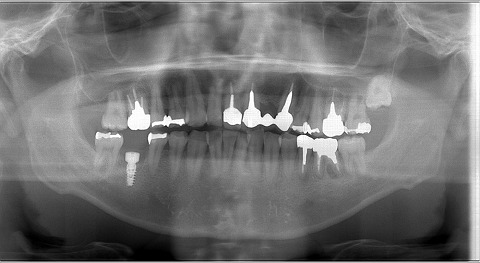

今日は、朝から 三件のオペでした。

今日は一日に6本埋入なのですが、3人で4部位 のため

立体的にずらして埋入しています。昔からの患者さまで。

意外と柔らかい下顎には時にはActiveを使用することもあります

ワイドのインプラントを入れるには骨幅が狭い為、力技でActiveを使用